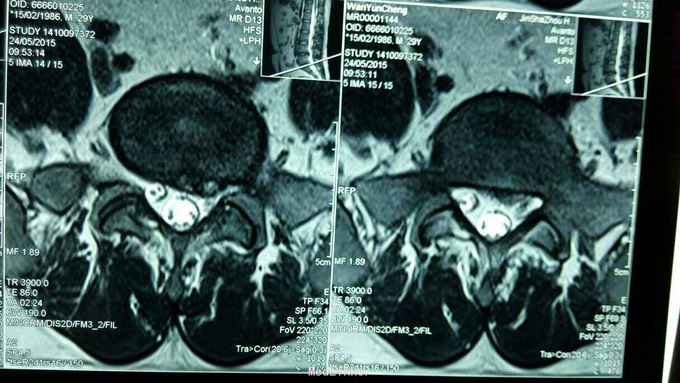

反复腰痛5年,再发5月,加重3天。 5年来反复出现腰部酸痛,未正规治疗,5个月前因腰痛不能下床,双下肢麻木,在针灸康复科住院治疗,疼痛减轻,出院休养,3天前再发腰痛,不能平躺,右下肢麻木入院。

步态正常,右侧椎间、椎旁压痛,右侧坐骨神经行程压痛,向下肢后缘放射,右侧髌腱反射、跟腱反射减弱,肌力正常。

腰椎间盘突出症,骶管囊肿 在神经阻滞麻醉下行,后路腰4~5椎间盘摘除术,骶管囊肿切开引流,神经根外膜松解术。 术后患者腰痛,右下肢麻木缓解。

骶管囊肿切开引流复发记几率如何?神经根瘤样变能否消退。右下肢因病变神经根引起麻木再发几率?